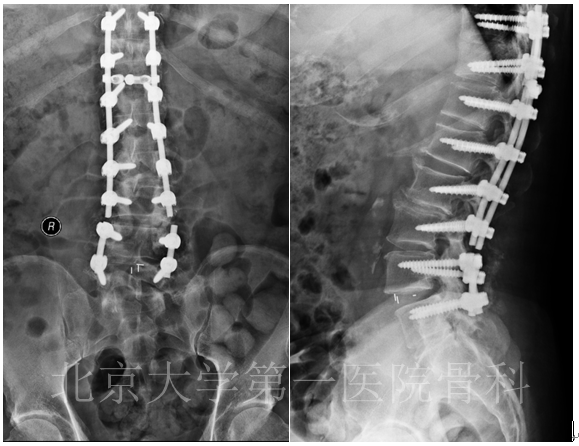

女性,71岁,主因腰部及双下肢疼痛半年,加重1月入院。患者半年前无明显诱因出现腰部疼痛,伴双下肢疼痛及左下肢麻木,范围为大腿外侧及小腿后外侧,休息后略缓解。1月前患者无明显诱因左下肢疼痛麻木明显加重,不能行走。保守治疗止疼药副反应明显。目前无法站立,VAS评分8分,ODI评分 64分。

既往史:溶血性贫血20余年,长期服用激素治疗,血色素正常。帕金森病10余年。7年前因T10压缩性骨折行PVP术。4年前胸部外伤致左第5-6肋骨折。

查体:脊柱后凸畸形。L5水平扣痛(+)。四肢肌张力高,可见不自主震颤。双下肢感觉、肌力、反射对称。双侧直腿抬高试验(-),双侧股神经牵拉试验(-)。

患者合并腰椎管狭窄症、帕金森病、骨质疏松症。考虑患者溶血性贫血,长期服用激素,骨质疏松严重,内固定禁忌明显,经讨论,决定予患者微创手术治疗。术后患者症状缓解明显。